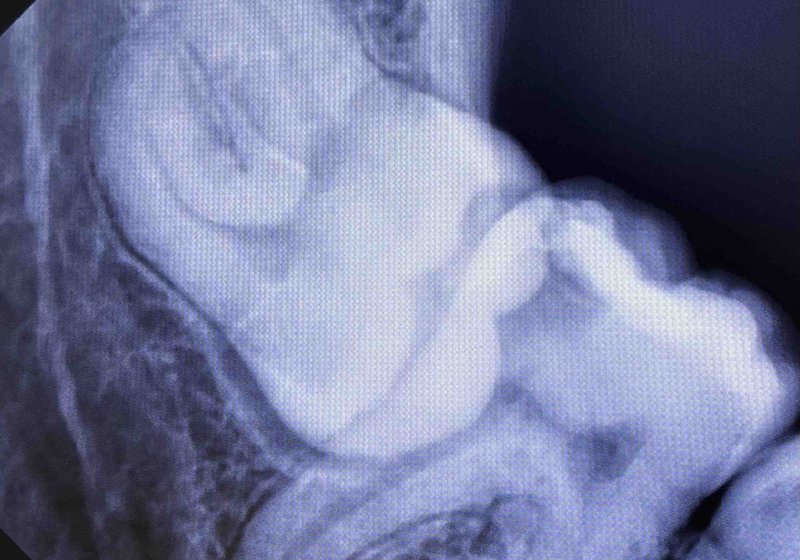

Wisdom tooth extraction

During: